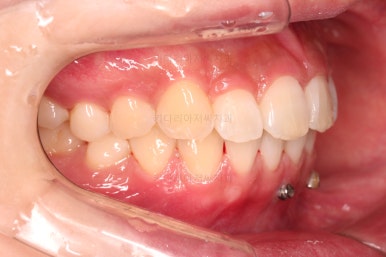

중간중간 미니스크류가 빠지든, 위치적으로 좋은 곳을 선택하든 여러 이유로 미니스크류 재식립이 몇 번 있었고요.

부족한 공간은 치간삭제를 통해서 만들어 나갑니다.

디테일을 위해서 윗니는 어금니에도 하나씩 장치를 더 부착했고, 아랫니는 바로 뒷 치아에도 장치를 부착했습니다.

과개교합 개선에 미니스크류까지 사용되었던 터라 매우 난이도가 높은(전체교정보다 훨씬 난이도가 높습니다.) 부산앞니부분교정이어서 1년여의 기간이 걸렸는데요.

기왕(부분교정임을 감안했을 때) 오래 걸린거 좀 더 완성도를 높이고자 아래 앞니는 설측교정까지 부착했습니다.

역시 미니튜브 장치를 이용했고, 아래 앞니 안쪽에다가 장치를 부착해서 아주 미세한 배열을 맞춰드렸습니다.